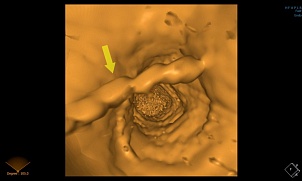

3D- реконструкция при исследовании пищеварительной системы: (Виртуальная гастро; колоноскопия)

Виртуальная колоноскопия — это метод лучевой диагностики, позволяющий визуализировать отделы толстой кишки. Виртуальная гастроскопия, аналогичный метод позволяе…